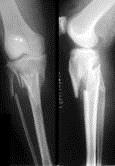

问题 病历摘要: 患者×××,男性,65岁,因车祸致伤左小腿后肿胀、活动受限、疼痛2小时。查体:左小腿上端肿胀,触痛(+),触及在骨擦音,左足伸足母、伸趾功能正常,足背动脉搏动正常。 该患者治疗首选是:

选项 A、手术复位+石膏外固定 B、交锁髓内钉内固定 C、牵引疗法 D、手术复位+小夹板内固定 E、切开复位+钢板内固定

答案 E

解析 E